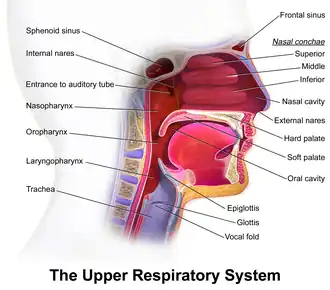

The Eustachian tube extends from the anterior wall of the middle ear to the lateral wall of the nasopharynx, approximately at the level of the inferior nasal concha. It consists of a bony part and a cartilaginous part.

The cartilaginous part of the Eustachian tube is about 24 mm in length and is formed of a triangular plate of elastic fibrocartilage, the apex of which is attached to the margin of the medial end of the bony part of the tube, while its base lies directly under the mucous membrane of the nasal part of the pharynx, where it forms an elevation, the torus tubarius or cushion, behind the pharyngeal opening of the auditory tube.

The position and relations of the pharyngeal opening are described with the nasal part of the pharynx. The mucous membrane of the tube is continuous in front with that of the nasal part of the pharynx, and behind with that of the tympanic cavity; it is covered with ciliated pseudostratified columnar epithelia and is thin in the osseous portion, while in the cartilaginous portion it contains many mucous glands and near the pharyngeal orifice a considerable amount of adenoid tissue, which has been named by Gerlach the tube tonsil.

The Eustachian tube also drains mucus from the middle ear. Upper respiratory tract infections or allergies can cause the Eustachian tube, or the membranes surrounding its opening to become swollen, trapping fluid, which serves as a growth medium for bacteria, causing ear infections. This swelling can be reduced through the use of decongestants such as pseudoephedrine, oxymetazoline, and phenylephrine.[15] Ear infections are more common in children because the tube is horizontal and shorter, making bacterial entry easier, and it also has a smaller diameter, making the movement of fluid more difficult. In addition, children's developing immune systems and poor hygiene habits make them more prone to upper respiratory infections.

Otitis media, or inflammation of the middle ear, commonly affects the Eustachian tube. Children under 7 are more susceptible to this condition, one theory being that this is because the Eustachian tube is shorter and at more of a horizontal angle than in the adult ear. Others argue that susceptibility in this age group is related to immunological factors and not Eustachian tube anatomy.